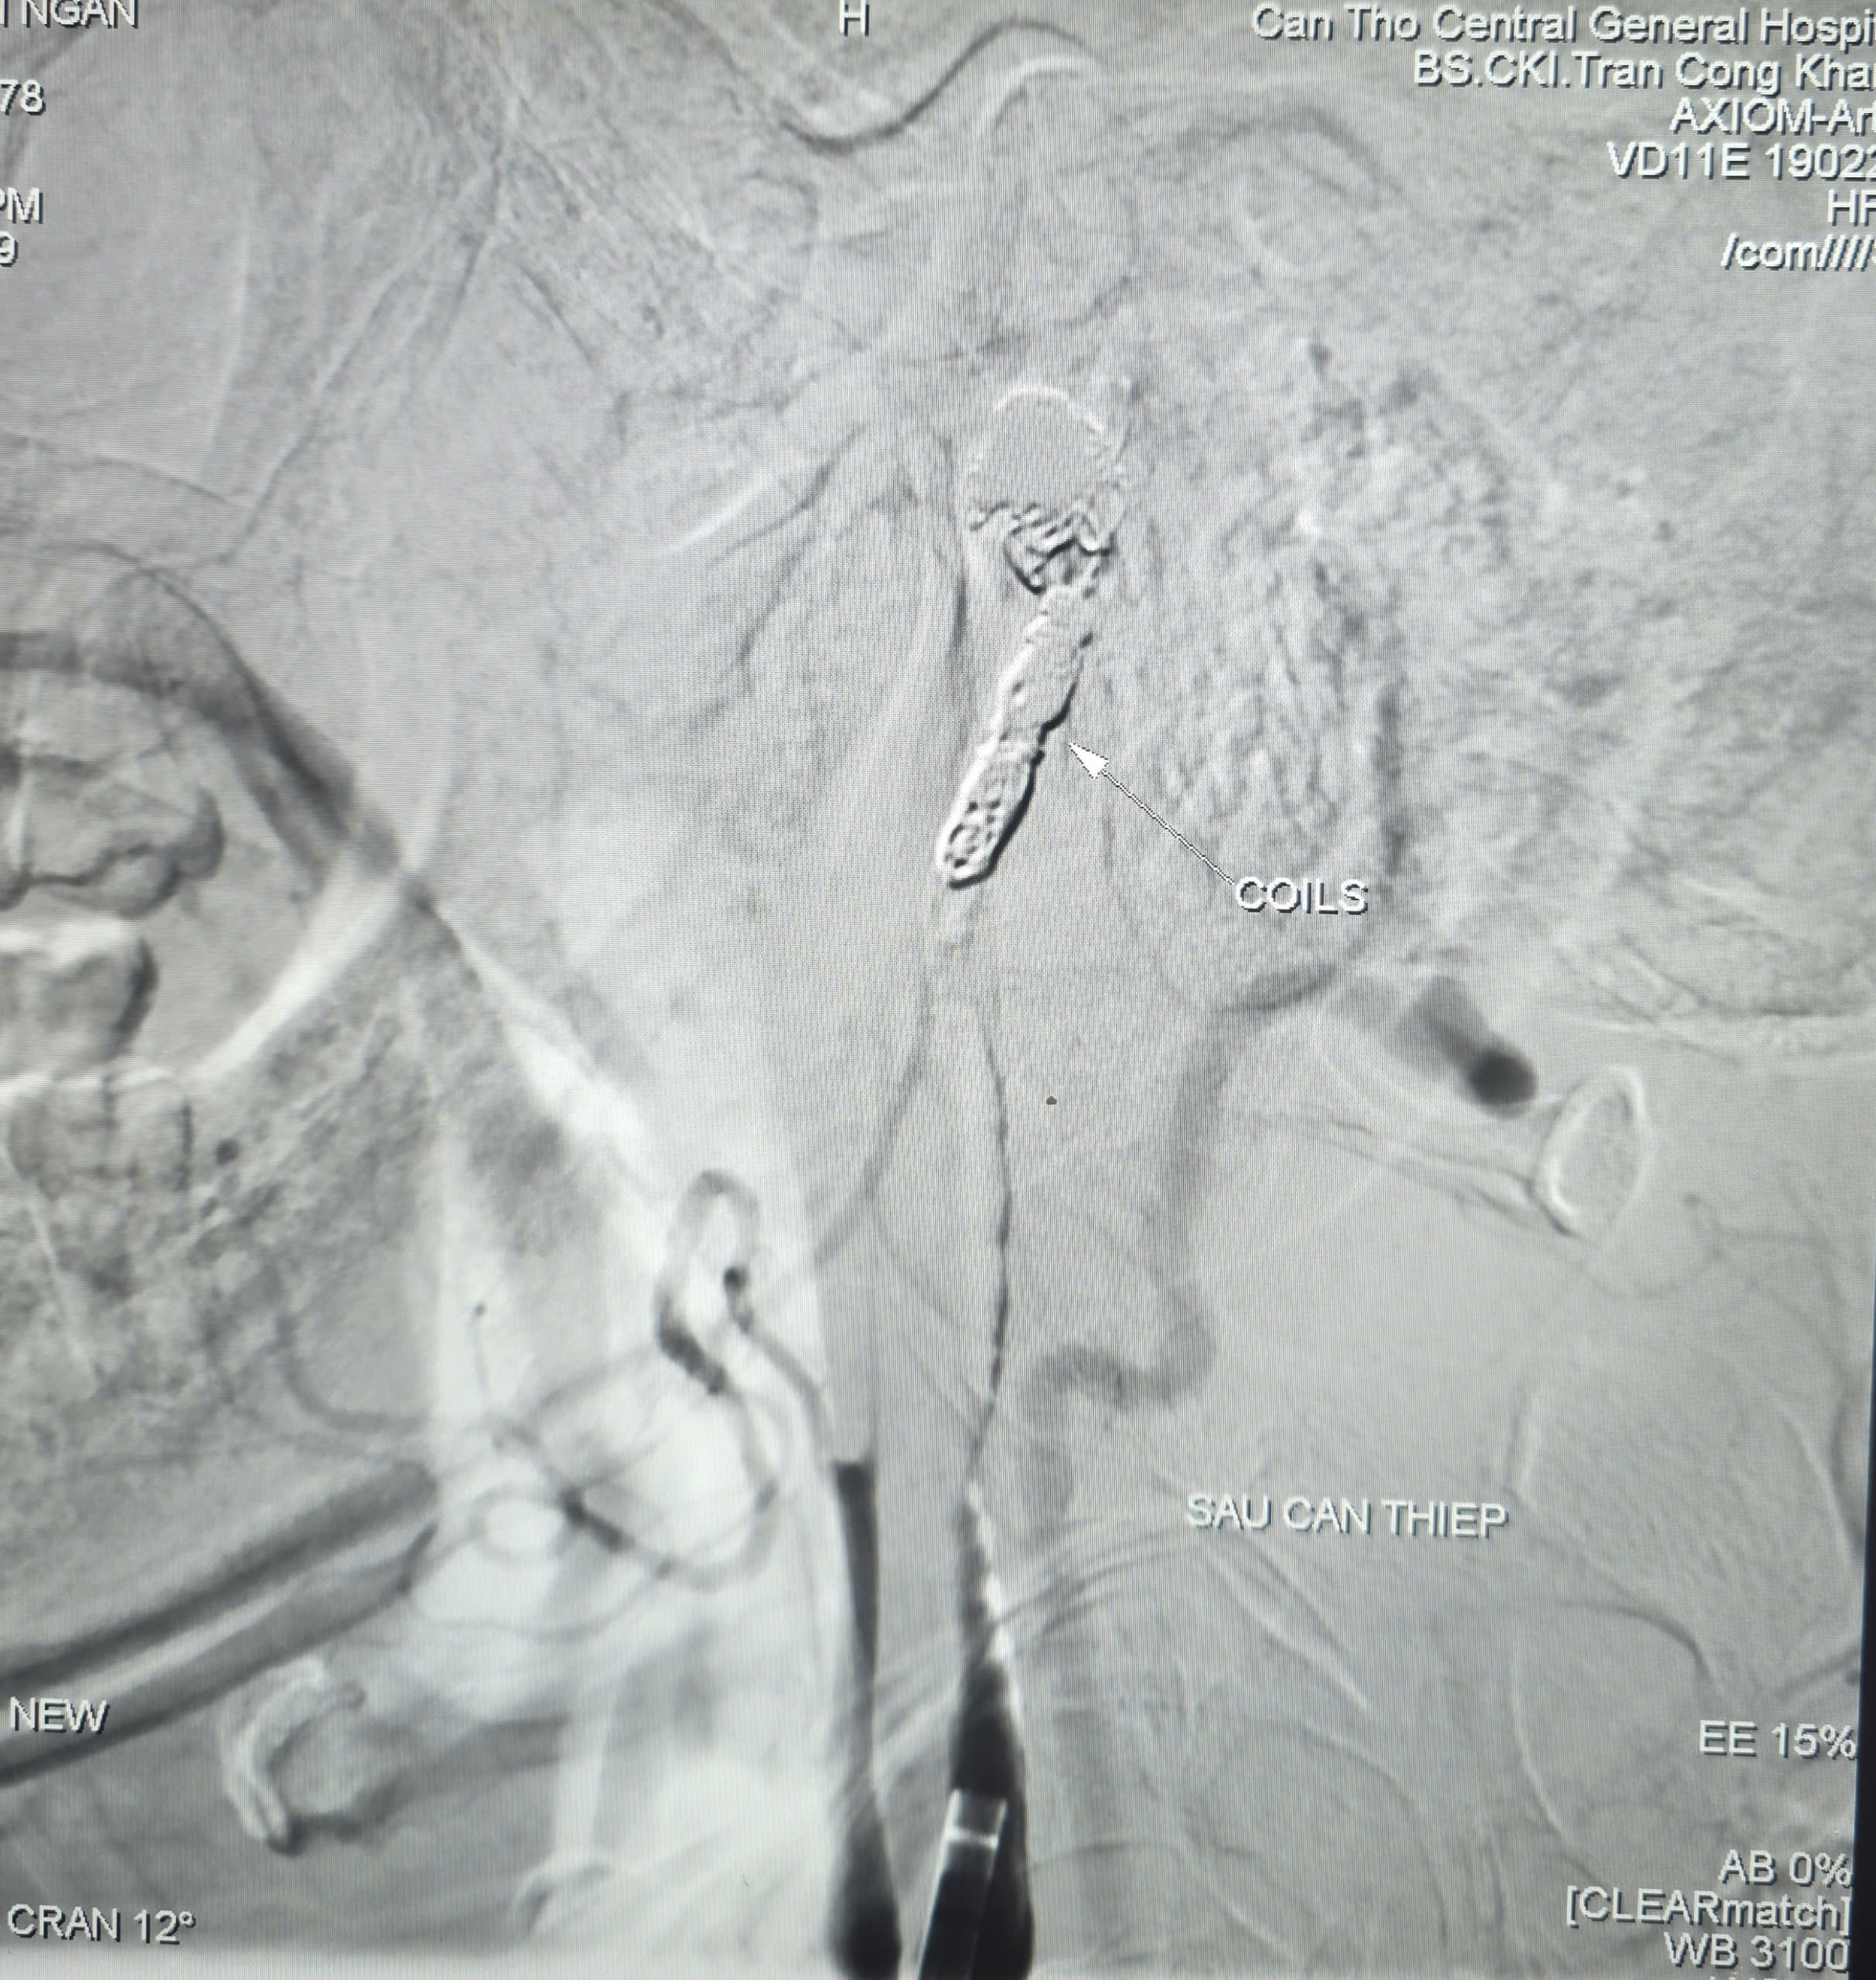

NÚT MẠCH CẤP CỨU BỆNH NHÂN K VÒM HẦU XUẤT HUYẾT Ồ ẠT BƯỚC TIẾN CHUYÊN SÂU TRONG CAN THIỆP MẠCH MÁU